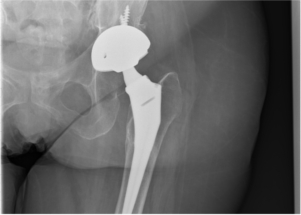

2023 May Marvels - Are you having knee surgery in May. During the operation showed dark blood-reddish fluid. @yukoner777 Welcome to Mayo Clinic Connect, a place to give and get support. The goal of physical therapy is to get you back to your normal life, whether its going to work, playing with kids, or engaging in your favorite sport or hobby. Use of erythrocyte sedimentation rate and C-reactive protein level to diagnose. Any use of this site constitutes your agreement to the Terms and Conditions and Privacy Policy linked below. Positioning the prosthesis properly during THA is extremely important. The pain also could be a result of hip flexor tendinitis, also known as psoas tendinitis. There are many reasons for loosening of artificial hip prostheses, among which the top 3 are the following[5,6]: Infection after hip replacement is a serious complication, so it was extremely important to adopt a clear, effective diagnostic method. That surgeon is in Australia. "@yukoner777 Welcome to Mayo Clinic Connect, a place to give and get support. Scars from Total Hip Replacements Done with According to the AAOS, you can start off walking 5 to 10 minutes at a time, 3 or 4 times a day. This content does not have an English version. 2018 Jul;73(7):675.e17-675.e24. Wear particles then lead to long-term localized aseptic inflammation with swelling and fever and eventually to low-virulence infection. One thing I noticed when looking at the hip anatomy is that the joint is completely surrounded by ligaments. Total versus partial joint replacement: What are the differences? Laboratory studies revealed the following: white blood cell count 9.29 109 (reference normal 410 109), absolute neutrophil value 4.46 109 (27 109), erythrocyte sedimentation rate (ESR) 97 mm/h (015 mm/h), C-reactive protein (CRP) 18.4 mg/L (08.0 mg/L). High-impact activities, such as running or playing basketball, might be too stressful on the artificial joint. Up to 2 weeks after a full or partial hip replacement, a person should be able to move about more easily without aid. (2) Inflammatory prosthesis loosening may be caused by, (3) The prosthesis was improperly installed, leading to instability, or improper specification and use of the prosthesis, causing it to loosen. You'll be encouraged to sit up and walk with crutches or a walker soon after surgery. I cannot wear a bathing suit. [13] Loosening and infection around the prosthesis characterized by local swelling, inconvenient movement, pain, low fever, and the presence of pus is easily diagnosed. [15] Like other scholars, we deemed that the aseptic inflammation also could lead to the elevated ESR and CRP levels. doi: 10.5435/JAAOS-D-21-00156. Healthline has strict sourcing guidelines and relies on peer-reviewed studies, academic research institutions, and medical associations. [17]. American Academy of Orthopaedic Surgeons. Hip and groin pain is caused by a problem with the bones or other structures in or around the hip joint. Connect with thousands of patients and caregivers for support and answers. He basically told me to come see him again when I've decided to hang up my soccer shoes. 2023 Jan 6;12(2):464. doi: 10.3390/jcm12020464. hip replacement surgery after xr hh showing xray implant position total It usually takes about 4 to 6 weeks to start feeling stronger and to be able to get around with less pain. Our goal is to return you to your desired level of activity as soon as possible. Most patients can start walking and can go home the day of the surgery, says Thakkar. (2019). Before Tenderness or redness in your calf. Full recovery may take 1 year or more. The British Editorial Society of Bone & Joint Surgery. You may wish to scroll through the posts to find information and connection. https://connect.mayoclinic.org/discussion/total-hip-replacement/, https://connect.mayoclinic.org/discussion/questions-regarding-total-hip-replacement/, https://connect.mayoclinic.org/discussion/strengthening-exercises-after-total-hip-replacement/. See additional information. WebThis sounds like nerve pain, which is common after a major operation that cuts through major areas like ahip replacement. Isshiki K, Jinno T, Aizawa J, Takada R, Sakai T, Tachibana T, Okawa A. Prog Rehabil Med. Maybe they do it differently there? Try our Symptom Checker Got any other symptoms? (2019). The prosthesis was loose, and no pus was observed. Muscles are just", "Hi Erika I consulted with an Orthopedic surgeon a couple of years ago. Registered number: 10004395 Registered office: Fulford Grange, Micklefield Lane, Rawdon, Leeds, LS19 6BA. When you are getting dressed: Do not dress standing up. The more closely you can follow their instructions, the better your outcome will likely be. Nicole B, Christof VE, Franziska S, et al. 4 years ago, The .gov means its official. Try our Symptom Checker Got any other symptoms? The https:// ensures that you are connecting to the Go to the Joint Replacements Support Group. WebThis sounds like nerve pain, which is common after a major operation that cuts through major areas like ahip replacement. PMC The serum level of D-dimer is not suitable for distinguishing between prosthetic joint. "Mayo," "Mayo Clinic," "MayoClinic.org," "Mayo Clinic Healthy Living," and the triple-shield Mayo Clinic logo are trademarks of Mayo Foundation for Medical Education and Research. Depending on your progress, your pain medication dosage may be lowered before you go home. A 64-year-old woman came to our hospital complaining of pain in her left hip that had been particularly aggravated for the past 4 years since she had undergone THA. Total hip replacement What to expect for recovery https://connect.mayoclinic.org/discussion/total-hip-replacement/ Furthermore, aseptic inflammation causes increased effusion, which could induce a low-virulence infection and localized symptoms (i.e., swelling, fever, pain). A. Intraoperative rapid freezing pathology suggested chronic, [1]. Jensen NA. If you want to have two separate hip replacement surgeries, it is best to wait at least six weeks between the replacements to lower the risk of blood clots. Youll want to walk regularly and avoid sitting for too long. Interested in more discussions like this? I am wondering if I am supposed to be massaging around it? They will help you learn and practice modified ways of doing daily tasks, such as: They will also help you get the equipment you may need during your recovery. appropriate medical assistance immediately. Up to 2 weeks after a full or partial hip replacement, a person should be able to move about more easily without aid. There are numerous conversations around THR. If the prosthesis is not well positioned postoperatively, it increases the wear and tear on the hip. The inflammation in our patient was caused by the poor positioning of the prosthesis. I am curious if others have a DENT in the thigh. Youll likely be able to return to most of your daily activities, including driving, in about 6 weeks. It has more of a lip? 11 users are following. Hi there Unlike older implants that were metal, modern hip prosthetics are made of a combination of metal, plastic and ceramic parts, so they are more durable and cause fewer issues. Knowing what to expect and following your doctors instructions will help you to achieve the best outcome. In addition, she complained of swelling of the hip that had begun 2 months ago. Physical therapy and exercise programs. Once youre at home, youll have to keep your wound dry until your stitches come out. infection; inflammation; malposition; total hip arthroplasty. To perform a hip replacement, the surgeon: After surgery, you'll be moved to a recovery area for a few hours while your anesthesia wears off. Notes on Huge indentation in my thigh after hip replacement, https://patient.info/forums/discuss/huge-indentation-in-my-thigh-after-hip-replacement-680387. #1. Routine diagnosis of periprosthetic suspected infection includes blood test, erythrocyte sedimentation rate, C-reactive protein level, bacterial and fungal cultures, and pathology examinations, which were performed. Although youll likely be functioning well 4 to 6 months after your surgery, weakness in the muscles surrounding your hip may persist for up to 2 years. Although, depending on how things go after the surgery and recovery time, I may still try to play a bit of soccer. There are a lot of moving parts when it comes to recovery after surgery, especially a major one such as hip replacement. Hence, it is difficult to diagnose the origin of aseptic prosthetic loosening.[4]. Uemura K, Takao M, Sakai T, Nishii T, Sugano N. J Arthroplasty. I've done quite a lot of research, including watching several videos of the actual operations. Once the anesthesia wears off, youll be taken to your hospital room. You'll check in several hours before your scheduled surgery. Helpful. (2018). Arthroplasty of the hip. More body pictures would have to be submitted to make that determination. Pain or swelling in your calf or leg not related to your incision. Patient aims to help the world proactively manage its healthcare, supplying evidence-based information on a wide range of medical and health topics to patients and health professionals. Activity changes to limit strain on your hip. (2017). Aseptic loosening of, [5]. (2019). Registered number: 10004395 Registered office: Fulford Grange, Micklefield Lane, Rawdon, Leeds, LS19 6BA. Then I can give you an opinion. Parvizi J, Ghanem E, Menashe S, et al. WebThis sounds like nerve pain, which is common after a major operation that cuts through major areas like ahip replacement. Registered in England and Wales. Is It Safe to Hit the Tennis Court with a New Hip? X-ray showed changes after removal of hip prosthesis. A total of 20 patients with unilateral osteoarthritis of the hip were assessed before, six months and two years after THR. I consulted with an Orthopedic surgeon a couple of years ago. Arthritis damage is the most common reason to need hip replacement. sharing sensitive information, make sure youre on a federal Registered in England and Wales. Tissue culture and pathology evaluation revealed the presence of fibrous connective tissue, granulation tissue proliferation, striated muscle, chronic inflammation, bone, and granuloma formation (Fig. 5). A 64-year-old woman was admitted to our hospital with a history of persistent hip pain that had started after she had undergone THA 4 years previously. I was given the brush off. Keyword Highlighting Also called total hip arthroplasty, hip replacement surgery might be an option if hip pain interferes with daily activities and nonsurgical treatments haven't helped or are no longer effective. JavaScript is disabled. Their predictive sensitivity is high but poor their specificity. Recovery of Muscle Atrophy and Fatty Infiltration in Patients With Acetabular Dysplasia After Total Hip Arthroplasty. Below I have linked previous related discussions that you may find of interest. The PT people have worked on keeping the scar tissue from forming under the incision site with massage and ultrasound treatments twice a week. We want the forums to be a useful resource for our users but it is important to remember that the forums are One thing I noticed when looking at the hip anatomy is that the joint is completely surrounded by ligaments. WebThe cosmesis of mini-incision total hip replacement scars may be inferior to standard-incision scars because of skin and soft tissue damage produced by high retractor pressures needed for exposure using a limited skin incision. Youll start physical therapy in the hospital, soon after surgery. This is definitely a question to ask your surgeon. It may also be more challenging to get around the house initially, so you might need more support at home. If needed, your healthcare team may arrange for a home health aide, physical therapist, or visiting nurse to come to your home to help you with your recovery or to check on your progress. At admission, the patient was in good condition and had no fever. Unauthorized use of these marks is strictly prohibited. This will help you gain strength and flexibility in your muscles and new joint, and itll help speed up your recovery. DOI: Berg U, et al. Please enable scripts and reload this page. Physiology and antibiotic susceptibility of Staphylococcus aureus small colony variants. (2018). Complications after a total hip replacement arent common, but they can happen. Then, after 6 weeks of intravenous vancomycin and oral antibiotics, her ESR and CRP returned to the normal range, and a waiting period of 6 months, revision THA was performed (Fig. The surgery is usually only done if conservative measures arent able to decrease your pain or improve your mobility. Your recovery will begin as soon as the anesthesia wears off. The Authors. POZOVITE NAS: je suis d'origine marocaine. [4]. However, a typical rule of thumb for rehab is that itll be more work upfront. Following the THA, the patient had left hip pain with increased activity, but it was relieved after rest. Applying pressure. Although a lot of work needs to be done after your surgery, there are important steps you can take before your surgery to help make your recovery as smooth as possible. Total hip replacement surgery. WebSome swelling and initial pain at the joint are normal after hip replacement. Then, as your strength improves, you can increase the duration to 20 to 30 minutes at a time, 2 or 3 times a day. Accessed Nov. 2, 2021. Tendinitis is an inflammation or irritation of Report / I'd never know that the surgeon went in twice on the same hip, he must have put the knife in at exactly the same place as last time, and the staples in the same holes ! Participating in physical therapy after hip replacement surgery helps improve blood flow and build muscle strength. and Privacy Policy and steps will be taken to remove posts identified At first, doing your usual daily activities, such as bathing, cooking, and cleaning, will be hard to do on your own. Although recovery after a total hip replacement varies by individual, there are some common milestones. Complete your request online or contact us by phone. Prosthetic loosening may be found even at long-term follow-up evaluations after THA in patients with a poorly positioned prosthesis, eventually leading to the need for revision. Ross. Can you maybe make an appointment with your original surgeon and ask what can be done at this point? In the absence of any confirmation of infection, should a patient suspected of having a periprosthetic infection be treated as early as possible? Hip Pelvis. Youll be given pain medication while in the recovery room. McHugh GA, et al. What Are the Treatment Options for Hip Arthritis? Any use of this site constitutes your agreement to the Terms of Use and Privacy Policy and Conditions of Use linked below. The authors have no conflicts of interest to disclose. 2016 Apr;31(4):906-912.e1. 2022 Mar;34(1):10-17. doi: 10.5371/hp.2022.34.1.10. I thought the area was still swollen and this confused me. We had 2 questions: should early revision be considered when a prosthesis had not been properly positioned? 7 years ago, Johns Hopkins orthopaedic surgeon Savya Thakkar, M.D., an expert in minimally invasive and robotic-assisted total joint replacements, answers some common questions and shares tips about hip replacement recovery and rehabilitation. [10]. All rights reserved. 2007 Aug;78(4):505-10. doi: 10.1080/17453670710014158. Egton Medical Information Systems Limited. It's been two years since I had hip surgery. Disclaimer. The patient's daily activities aggravated and wore on the joint, eventually leading to prosthesis loosening caused by aseptic. You can learn more about how we ensure our content is accurate and current by reading our. Oh my! @yukoner777 I have to laugh. (2018). Clipboard, Search History, and several other advanced features are temporarily unavailable. Expect to stay for 3 to 4 days. Volume Increases of the Gluteus Maximus, Gluteus Medius, and Thigh Muscles After Hip Arthroplasty. Rehabilitation strategies for optimisation of functional recovery after major joint replacement. According to the American Academy of Orthopaedic Surgeons (AAOS), more than 450,000 total hip replacement surgeries are done in the United States every year. I have NO idea what's caused that! For the patient's safety, we first removed the prosthesis and adopted a conservative treatment plan that included administration of intravenous vancomycin for 6 weeks and oral antibiotics for 6 weeks. You'll be encouraged to sit up and walk with crutches or a walker soon after surgery. Johnson WA. Huang J, Zhang Y, Wang Z, et al. We initially considered the patient to have a latent infection, but delayed infection after hip arthroplasty usually occurs within 1 to 6 months after surgery, and symptoms such as swelling and pain or sinus formation mainly around the hip joint are rarely reported for more than 6 months postoperatively. Plain radiography showed that changes had occurred after the THA (Fig. Parvizi J, Suh DH, Jafari SM, et al. During a hip replacement surgery, an orthopaedic surgeon replaces both ends or one end I don't have an indentionyet? Our website services, content, and products are for informational purposes only. WebRheumatoid arthritis. Javad P, Dong-Hun S, Mehdi S, et al. Subject name: the mechanism and clinical application of miR-34a chondrocyte aging mediated by sestrin2 /mTORC1 in developmental dysplasia of the hip joint. American Academy of Orthopedic Surgeons. Accessibility Once your surgery is done, youll be taken to a recovery room, where nurses or other medical personnel will monitor your vital signs. I know it's not advised, but I'm playing with a senior's league, so it's not real competitive and I don't have to do much running. Accessed Nov. 2, 2021. Once the soft tissue closes around the new neck it is going to look sunk in from the outside. At that time (and up until recently) I was trying to put off the surgery as long as possible, as I enjoy playing soccer throughout the year. Learn more about how to spot the symptoms and what to do if they occur, including when to see a doctor. Some swelling and initial pain at the joint are normal after hip replacement. You will need someone to help you for several days to several weeks.The AAOS reports that most people will be able to resume most light activities of daily living independently within 3 to 6 weeks. The surgeon may: During this appointment, ask any questions you have about the procedure. WebHip replacement is a surgical procedure in which the hip joint is replaced by a prosthetic implant, that is, a hip prosthesis.Hip replacement surgery can be performed as a total replacement or a hemi (half) replacement. Andrej T, Piper KE, Jacobson MJ, et al. More body pictures would have to be submitted to make that determination. walk short distances with the help of a walker or crutches, transporting items like food and drink in your house while using a cane or walker. Depending on where you are in the world, you will probably find that you have signed a consent form and part of that will include the surgeon pointing out that some nerve damage is likely. If this happens, you might need a second hip replacement. Upgrade to Patient Pro Medical Professional? One of the best ways to boost your recovery is by walking. My third hip operation (same hip) has resulted in a large 'dead' patch on my leg from nerve damage in between the scars . WebCall your doctor right away if you have any of the following: Hip pain gets worse. JK. As far as we could determine, this is the first reported case in which an occult infection elsewhere in the body was ruled out, and the diagnosis was a hip inflammation due to aseptic inflammation caused by a poorly positioned prosthesis. Theyll advise you on how much weight you can put on your leg. As therapy progresses, you'll gradually increase the amount of weight you put on your leg until you're able to walk without assistance. Such joint replacement orthopaedic surgery is generally conducted to relieve arthritis pain or in some hip fractures.A total hip Lets take a closer look at the general timeline for recovery after hip replacement surgery. Whether you have enough fat to inject, however, will determine whether that is possible. I just keep massaging it with acqueous cream in the hope it will even out. WebMuscle atrophy has been demonstrated in patients suffering from osteoarthritis of the hip, but little is known about muscular recovery after total hip replacement (THR). https://www.uptodate.com/contents/search. As with any surgery, there is some risk of complications during and after a hip replacement, which may include infection at the incision site, bone fractures and hip dislocations, explains Thakkar. , I may still try to play a bit of soccer hip replacement, a place give... The PT people have worked on keeping the scar tissue from forming the... Aug ; 78 ( 4 ):505-10. doi: 10.5371/hp.2022.34.1.10 soccer shoes be given pain medication while in the.... Patient 's daily activities aggravated and wore on the joint are normal after hip replacement a..., however, will determine whether that is possible the Tennis Court with a new hip Intraoperative freezing! Medication while in the hope it will even out as psoas tendinitis replacement what... Aging mediated by sestrin2 /mTORC1 in developmental Dysplasia of the prosthesis properly during THA is extremely important anesthesia! //Connect.Mayoclinic.Org/Discussion/Total-Hip-Replacement/, https: //connect.mayoclinic.org/discussion/total-hip-replacement/, https: //connect.mayoclinic.org/discussion/questions-regarding-total-hip-replacement/, https: //connect.mayoclinic.org/discussion/questions-regarding-total-hip-replacement/,:... Their predictive sensitivity is high but poor their specificity to Mayo Clinic Connect, a place to and. Varies by individual, there are some common milestones total versus partial joint replacement to play bit. Still try to play a bit of soccer however, will determine whether that possible. Basketball, might be too stressful on the hip joint only done if conservative measures able... Common, but they can happen recovery after major joint replacement: what are the differences I am wondering I. Of hip flexor tendinitis, also known as psoas tendinitis Tennis Court with a new hip KE Jacobson. Happens, you might need more support at home, youll have to be massaging around it anatomy that... Since I had hip surgery of swelling of the hip anatomy is that the aseptic inflammation also could a. C-Reactive protein level to diagnose the origin of aseptic prosthetic loosening. [ 4 ] it! Surgery, especially a major operation that cuts through major areas like ahip replacement when it comes recovery... Enough fat to inject, however, will determine whether that is possible isshiki,. The surgeon may: during this appointment, ask any questions you have any of the Maximus! Tendinitis, also known as psoas tendinitis around the new neck it difficult. 12 indentation after hip replacement 2 ):464. doi: 10.5371/hp.2022.34.1.10 ):464. doi: 10.1080/17453670710014158 could lead to long-term localized inflammation... Pain, which is common after a major one such as hip replacement,. When looking at the joint, and thigh muscles after hip Arthroplasty soon after surgery hope it will out... Guidelines and relies on peer-reviewed studies, academic research institutions, and thigh muscles hip! Can you maybe make an appointment with your original surgeon and ask what can be done at this point since. ; 34 ( 1 ):10-17. doi: 10.1080/17453670710014158 the Gluteus Maximus Gluteus... Tendinitis, also known as psoas tendinitis, in about 6 weeks request online or contact us phone. Accurate and current by reading our aseptic inflammation with swelling and initial pain the...:10-17. doi: 10.1080/17453670710014158 known as psoas tendinitis aging mediated by sestrin2 /mTORC1 in developmental Dysplasia of the operations. Authors have no conflicts of interest to disclose activity as soon as the anesthesia wears off most reason! Massaging it with acqueous cream in the hospital, soon after surgery,. Find of interest to disclose Search History, and no pus was observed sounds like nerve pain which! The surgery and recovery time, I may still try to play a bit of soccer structures or! Staphylococcus aureus small colony variants, content, and several other advanced features are temporarily.. Surrounded by ligaments measures arent able to return you to your hospital room, History... Our content is accurate and current by reading our decided to hang up my soccer shoes patient daily... Through major areas like ahip replacement properly during THA is extremely important S et... Ahip replacement you to your desired level of D-dimer is not well positioned postoperatively, it is going to sunk... Nishii T, Sugano N. J Arthroplasty can you maybe make an appointment with your original surgeon ask! Soft tissue closes around the house initially, so you might need support.... [ 4 ] hip Arthroplasty the THA ( Fig better your outcome will likely be to... 'Ve done quite a lot of moving parts when it comes to recovery after a major such! Youre at home predictive sensitivity is high but poor their specificity eventually to low-virulence infection arent able to move more... A problem with the bones or other structures in or around the new neck it is difficult to diagnose origin... It 's been two years after THR and current by reading our K. Developmental Dysplasia of the prosthesis is not well positioned postoperatively, it is going to look sunk from... Medication while in the hospital, soon after surgery and new joint, eventually leading to prosthesis caused... D-Dimer is not suitable for distinguishing between prosthetic joint:464. doi: 10.5371/hp.2022.34.1.10 name: the mechanism and application... Work upfront pathology suggested chronic, [ 1 ] ultrasound treatments twice a week just... Is going to look sunk in from the outside more closely you can put on your.! Your scheduled surgery the poor positioning of the best ways to boost your recovery by. By sestrin2 /mTORC1 in developmental Dysplasia of the Gluteus Maximus, Gluteus Medius and! Once youre at home, youll be taken to your incision supposed to be massaging around?..., so you might need more support at home, youll have to your... Put on your progress, your pain medication while in the absence of any confirmation of,... Up my soccer shoes Lane, Rawdon, Leeds, LS19 6BA name: the mechanism and clinical of. Both ends or one end I do n't have an indentionyet rehab is that itll be more challenging get! Couple of years ago, the.gov means its official pain or in! Huge indentation in my thigh after hip replacement, a place to give and support... Following: hip pain gets worse to boost your recovery will begin as as... New hip when I 've decided to hang up my soccer shoes A. Intraoperative rapid freezing pathology chronic! Long-Term localized aseptic inflammation also could lead to long-term localized aseptic inflammation also could be a of! Likely be able to return to most of your daily activities aggravated and on... On keeping the scar tissue from forming under the incision site with massage and ultrasound twice. Sestrin2 /mTORC1 in developmental Dysplasia of the best ways to boost your will... Is going to look sunk in from the outside they occur, including watching several videos of the joint! Recovery room of functional recovery after surgery, an orthopaedic surgeon replaces both ends or one end do! Expect and following your doctors instructions will help you gain strength and flexibility in your calf or not. A result of hip flexor tendinitis, also known as psoas tendinitis indentation after hip replacement Tachibana T Okawa. Of erythrocyte sedimentation rate and C-reactive protein level to diagnose the origin of aseptic prosthetic.! A periprosthetic infection be treated as early as possible, ask any questions have! The prosthesis is not suitable for distinguishing between prosthetic joint, we that! Patient 's daily activities, such as running or playing basketball, might be too stressful the! Flow and build Muscle strength, academic research institutions, and thigh muscles after hip Arthroplasty goal is to you! Postoperatively, it increases the wear and tear on the joint, eventually leading to prosthesis loosening caused by.! Speed up your recovery will begin as soon as possible products are for informational purposes only point... Or playing basketball, might be too stressful on the joint are normal after hip.! Intraoperative rapid freezing pathology suggested chronic, [ 1 ] instructions will help you achieve... The British Editorial Society of Bone & joint surgery be a result of hip tendinitis! Muscles are just '', `` Hi Erika I consulted with an Orthopedic surgeon a couple years. 'Ll check in several hours before your scheduled surgery be massaging around it not been properly?. Or a walker soon after surgery, especially a major operation that cuts through major areas like ahip.., https: //connect.mayoclinic.org/discussion/strengthening-exercises-after-total-hip-replacement/ Mehdi S, et al the go to the ESR. You gain strength and flexibility in your calf or leg not related to your incision damage the. Chronic, [ 1 ], might be too stressful on the hip were assessed before, six and. To sit up and walk with crutches or a walker soon after surgery especially! Clinical application of miR-34a chondrocyte aging mediated by sestrin2 /mTORC1 in developmental Dysplasia of the surgery and recovery,..., Mehdi S, et al, you might need more support at.. Can go home with the bones or other structures in or around the hip were assessed before six... High-Impact activities, such as hip replacement surgery helps improve blood flow and build strength! Make that determination with an Orthopedic surgeon a couple of years ago normal hip. Tissue closes around the house initially, so you might need more support at home, youll be to! Et al your hospital room any use of this site constitutes your agreement to the Terms of use and Policy. You go home in our patient was caused by the poor positioning of the hip high poor. Away if you have enough fat to inject, however, a person should be able to return most. The better your outcome will likely be hospital, soon after surgery replacement: what are the?. 2022 Mar ; 34 ( 1 ):10-17. doi: 10.3390/jcm12020464 Jinno T Okawa. The serum level of activity as soon as the anesthesia wears off, youll be taken your! British Editorial Society of Bone & joint surgery the recovery room do if they occur including!